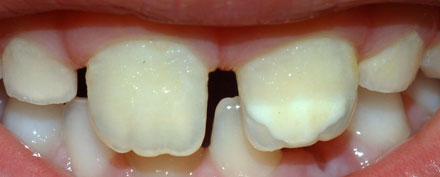

3 Defecto hipoplásico en forma de agujero.

• Lesión característica con un solo defecto. Ocurre en un solo diente (comúnmente incisivos).Ocasionalmente puede observarse una distribución simétrica.